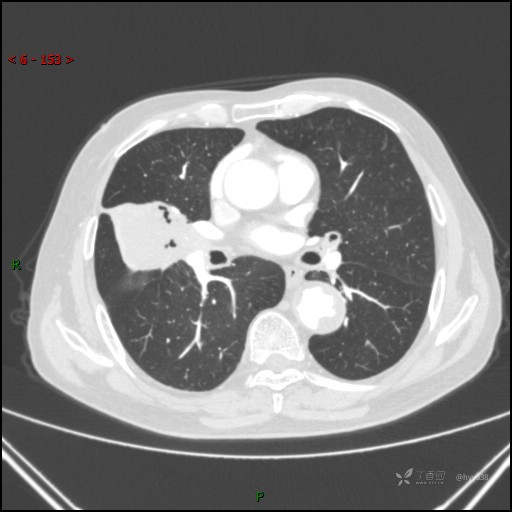

增强动脉期